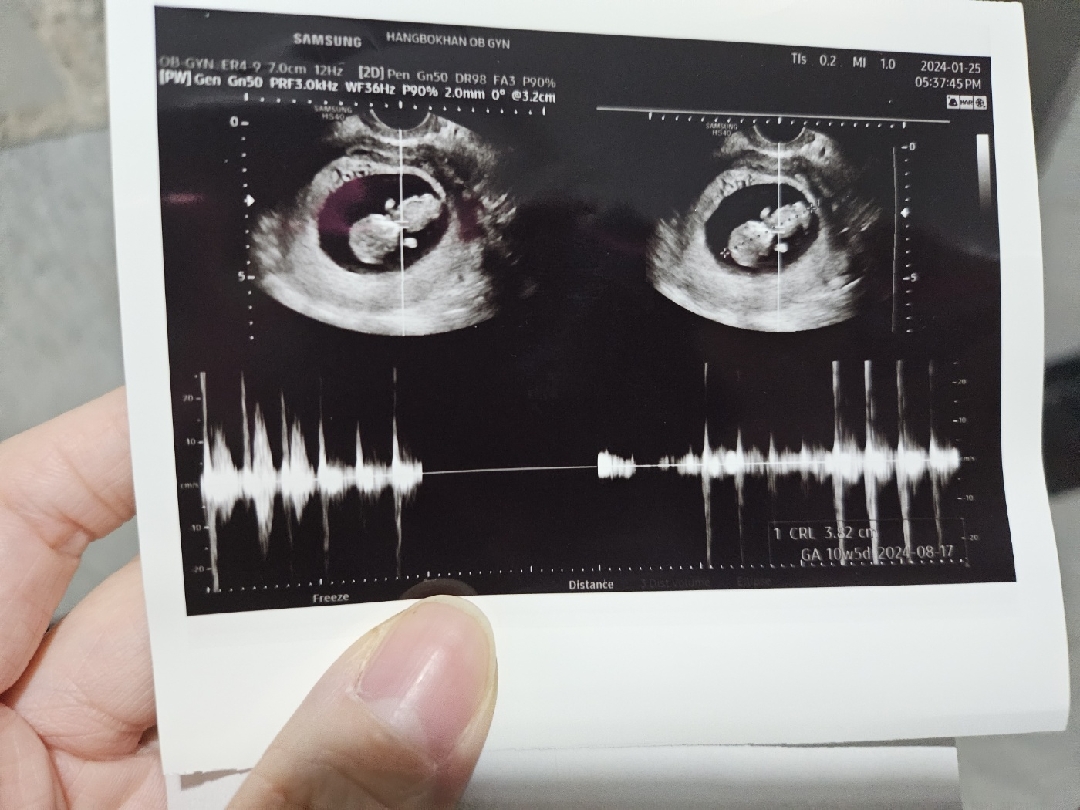

몇주에 크기가 얼만해요?

10주5일에 3.82센티라고 적혀있네용🙂

실제주수는..9주5일입니닷 헤헤😃